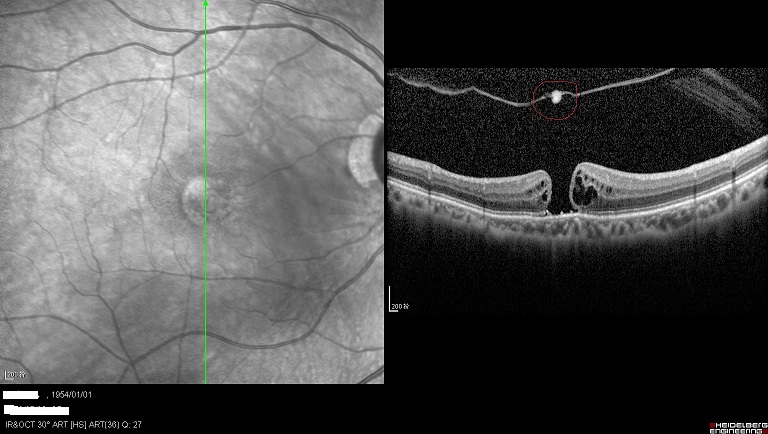

左眼黄斑被玻璃牵引黄斑即将形成裂孔

术后左眼黄斑已经复位

术后右眼的黄斑裂孔闭合